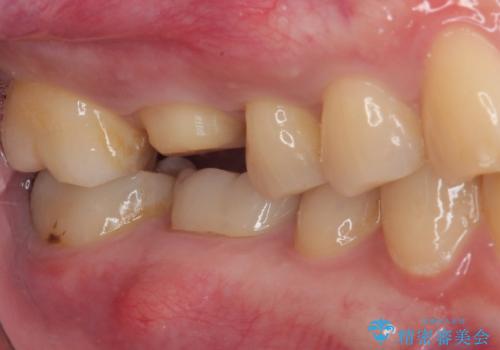

- 歯が割れたことを主訴に来院された患者様です。割れた原因としては噛み合う歯が強化セラミックスのみでできたフルジルコニアクラウンであったことと、大きな詰め物が入っていて自分自身の歯の範囲が少なかったことが考えられます。応急で来院されたときには暫間的に強力な接着剤で固定しました。

CT を撮影して確認したところ、歯肉より4ミリ程度深い場所で破折していました。患者様と相談して、外科的な介入はせずに被せもののみでの治療を行うこととしました。

拡大鏡視野下で詰め物と虫歯の除去を行い、詰め物の範囲が大きかったためオールセラミッククラウンに適した形に整えました。